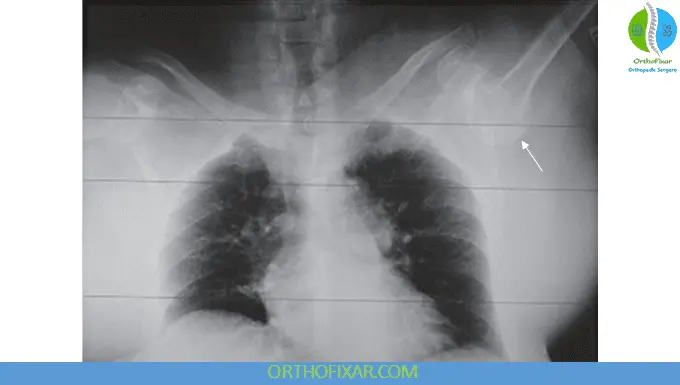

Radiographic Evaluation

A standard trauma shoulder series is required:

- Anteroposterior (AP) view

- Scapular-Y view

- Axillary view

Typical Findings:

- Inferior displacement of the humeral head

- Humeral shaft directed superiorly, often aligned with the glenoid margin

Careful assessment is crucial to detect associated fractures, which are common and may be masked by diffuse pain.